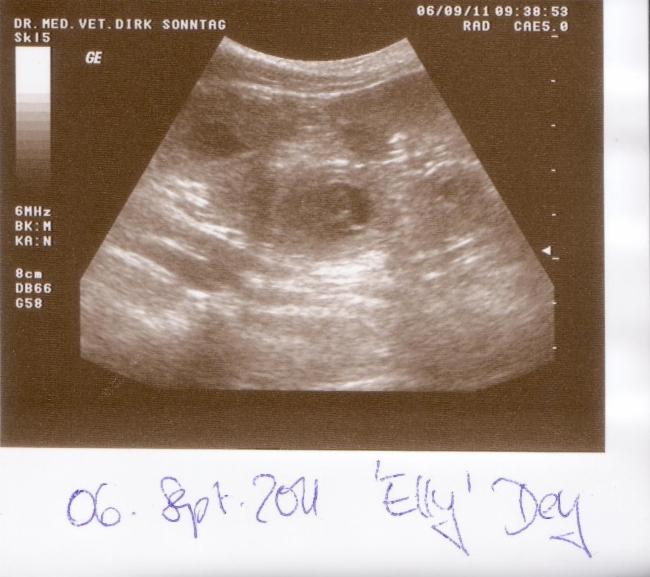

06.09.2011 Die Ultraschalluntersuchung

Der 26. Tag der Trächtigkeit war auch der Tag der Ultraschalluntersuchung. Er zeigte was ich schon lange wusste: Elena trägt die B-chen in sich. 10 Welpen konnten wir auf Anhieb entdecken. Wie viele es wirklich werden, wird Elena erst Mitte Oktober veraten, doch wer sich an den Ultraschall des A-Wurfes erinnert, kann sich denken das sich da vermutlich noch mehr B-chen in Elenas Bauch versteckt haben.

Stellvertretend für die anderen B-chen stellen wir hier schon mal die ersten vor: